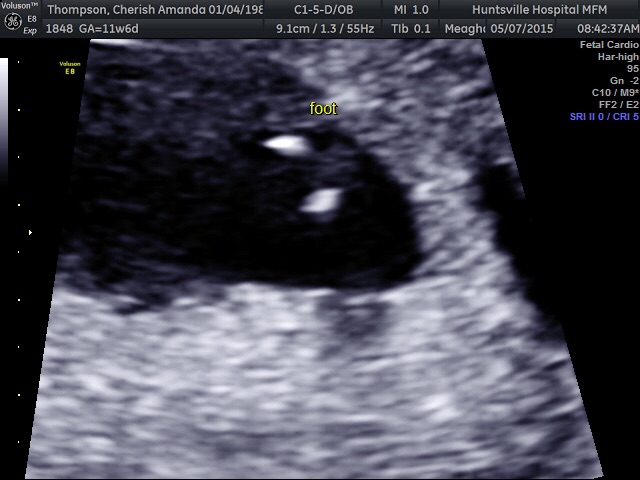

11 weeks and 2 days. This appointment was with my high risk specialist, I hope her nub theory guess was right :x so in love & super happy we got a 3d/4d.